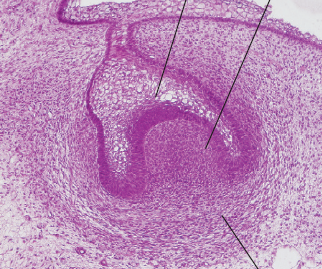

2. Cap stage

1. The epithelial bud continues to proliferate within the ectomesenchyme that it is embedded in

1. Condensation of the ectomesenchymal cells that surround the bud (forming the DENTAL PAPILLA)

2. We can clearly see the epithelial enamel organ sitting upon a section of condensed ectomesenchyme (the dental papilla)

1. Dental follicle limiting dental papilla and surrounding the enamel organ

2. Invasion of vascular supply to DP

1. Early bell stage (4 cell layers)

1. Cells on the periphery of the enamel organ assume a low cuboidal shape. This creates the outer enamel epithelium

1. Cells lining the dental papilla assume a short columnar shape. This creates the inner enamel epithelium (which later differentiate into ameloblasts)

1. The stratum intermedium forms via differentation of epithelial cells located between the IDE and SR. The cells have a characteristically high amount of alkaline phosphatase

2. Stellate reticulum